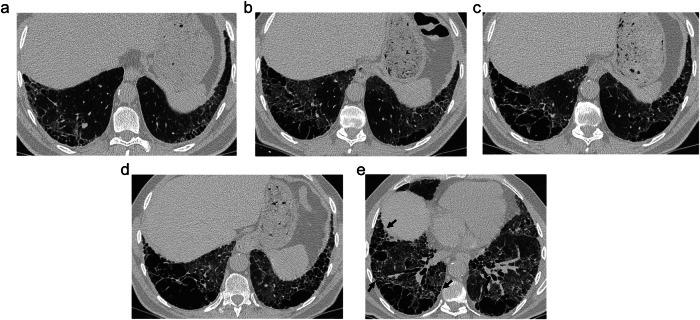

Due to destructive, fibrotic, and remodeling mechanisms, we can find a varied constellation of aerated and cystic lung lesions in smoker patients with interstitial lung disease that pose a diagnostic challenge for both radiologists and pathologists. Radiologic terminology used for cystic lung lesions in smokers is varied and sometimes confusing, and the same applies to their pathologic correlation, with different names for similar findings. Moreover, there is substantial overlap among different cystic lesions in both radiology and pathology. Ultimately, the diagnosis of a given type of cyst may lead to a wrong diagnosis with important clinical implications. In this setting, the goals of this article are to present a diagnostic approach to these lesions by correlating radiologic findings with pathology and describing a series of radiologic characteristics of these lesions, which we have called "the four S of cystic lung lesions in smokers" for size, site, shape, and surrounding of the lesions. We will define the clue radiological findings of centrilobular emphysema, paraseptal emphysema, thin-walled cysts, traction emphysema, honeycombing, smoking-related diffuse cystic lung disease, cysts in Langerhans cell histiocytosis, and cystic lesions appearing in desquamative interstitial pneumonia and we will try to show a correlation of each of these lesions with pathology for a better understanding of radiological findings. Finally, we will deal with fibrosing lung diseases and cystic lung lesions in smokers, specifically with smoking-related interstitial fibrosis and its pathological variants, and with usual interstitial pneumonia, whose prognosis is strikingly different. CRITICAL RELEVANCE STATEMENT: Knowledge of the pathological correlation of the different cystic lesions that appear in smokers with interstitial lung disease permits a better understanding of their radiological manifestations. KEY POINTS: Interstitial lung disease in smokers is characterized by varied cystic lung lesions. Cystic lesions are characterized by their size, site, shape, and surroundings. Cystic lesions in smokers may help to characterize the underlying fibrosing disease.

由于存在破坏、纤维化和重塑机制,我们在患有间质性肺病的吸烟患者中可发现多种不同类型的含气和囊性肺病变,这给放射科医生和病理科医生都带来了诊断挑战。用于描述吸烟患者囊性肺病变的放射学术语多种多样,有时令人困惑,其病理相关性也是如此,相似的表现有不同的名称。此外,不同的囊性病变在放射学和病理学上都有大量重叠。最终,对某一特定类型囊肿的诊断可能会导致错误诊断,产生重要的临床影响。在此背景下,本文的目的是通过将放射学表现与病理学相关联,提出针对这些病变的诊断方法,并描述这些病变的一系列放射学特征,我们将其称为“吸烟患者囊性肺病变的四个S”,即病变的大小、位置、形态和周围情况。我们将定义小叶中心型肺气肿、间隔旁肺气肿、薄壁囊肿、牵拉性肺气肿、蜂窝肺、吸烟相关弥漫性囊性肺疾病、朗格汉斯细胞组织细胞增多症中的囊肿以及脱屑性间质性肺炎中出现的囊性病变的关键放射学表现,并试图展示这些病变与病理学的相关性,以便更好地理解放射学表现。最后,我们将探讨吸烟患者的纤维化性肺病和囊性肺病变,特别是与吸烟相关的间质性纤维化及其病理变体,以及预后截然不同的普通间质性肺炎。关键相关性声明:了解吸烟合并间质性肺病患者出现的不同囊性病变的病理相关性有助于更好地理解其放射学表现。关键点:吸烟患者的间质性肺病以多种囊性肺病变为特征。囊性病变以其大小、位置、形态和周围情况为特征。吸烟患者的囊性病变可能有助于明确潜在的纤维化疾病。